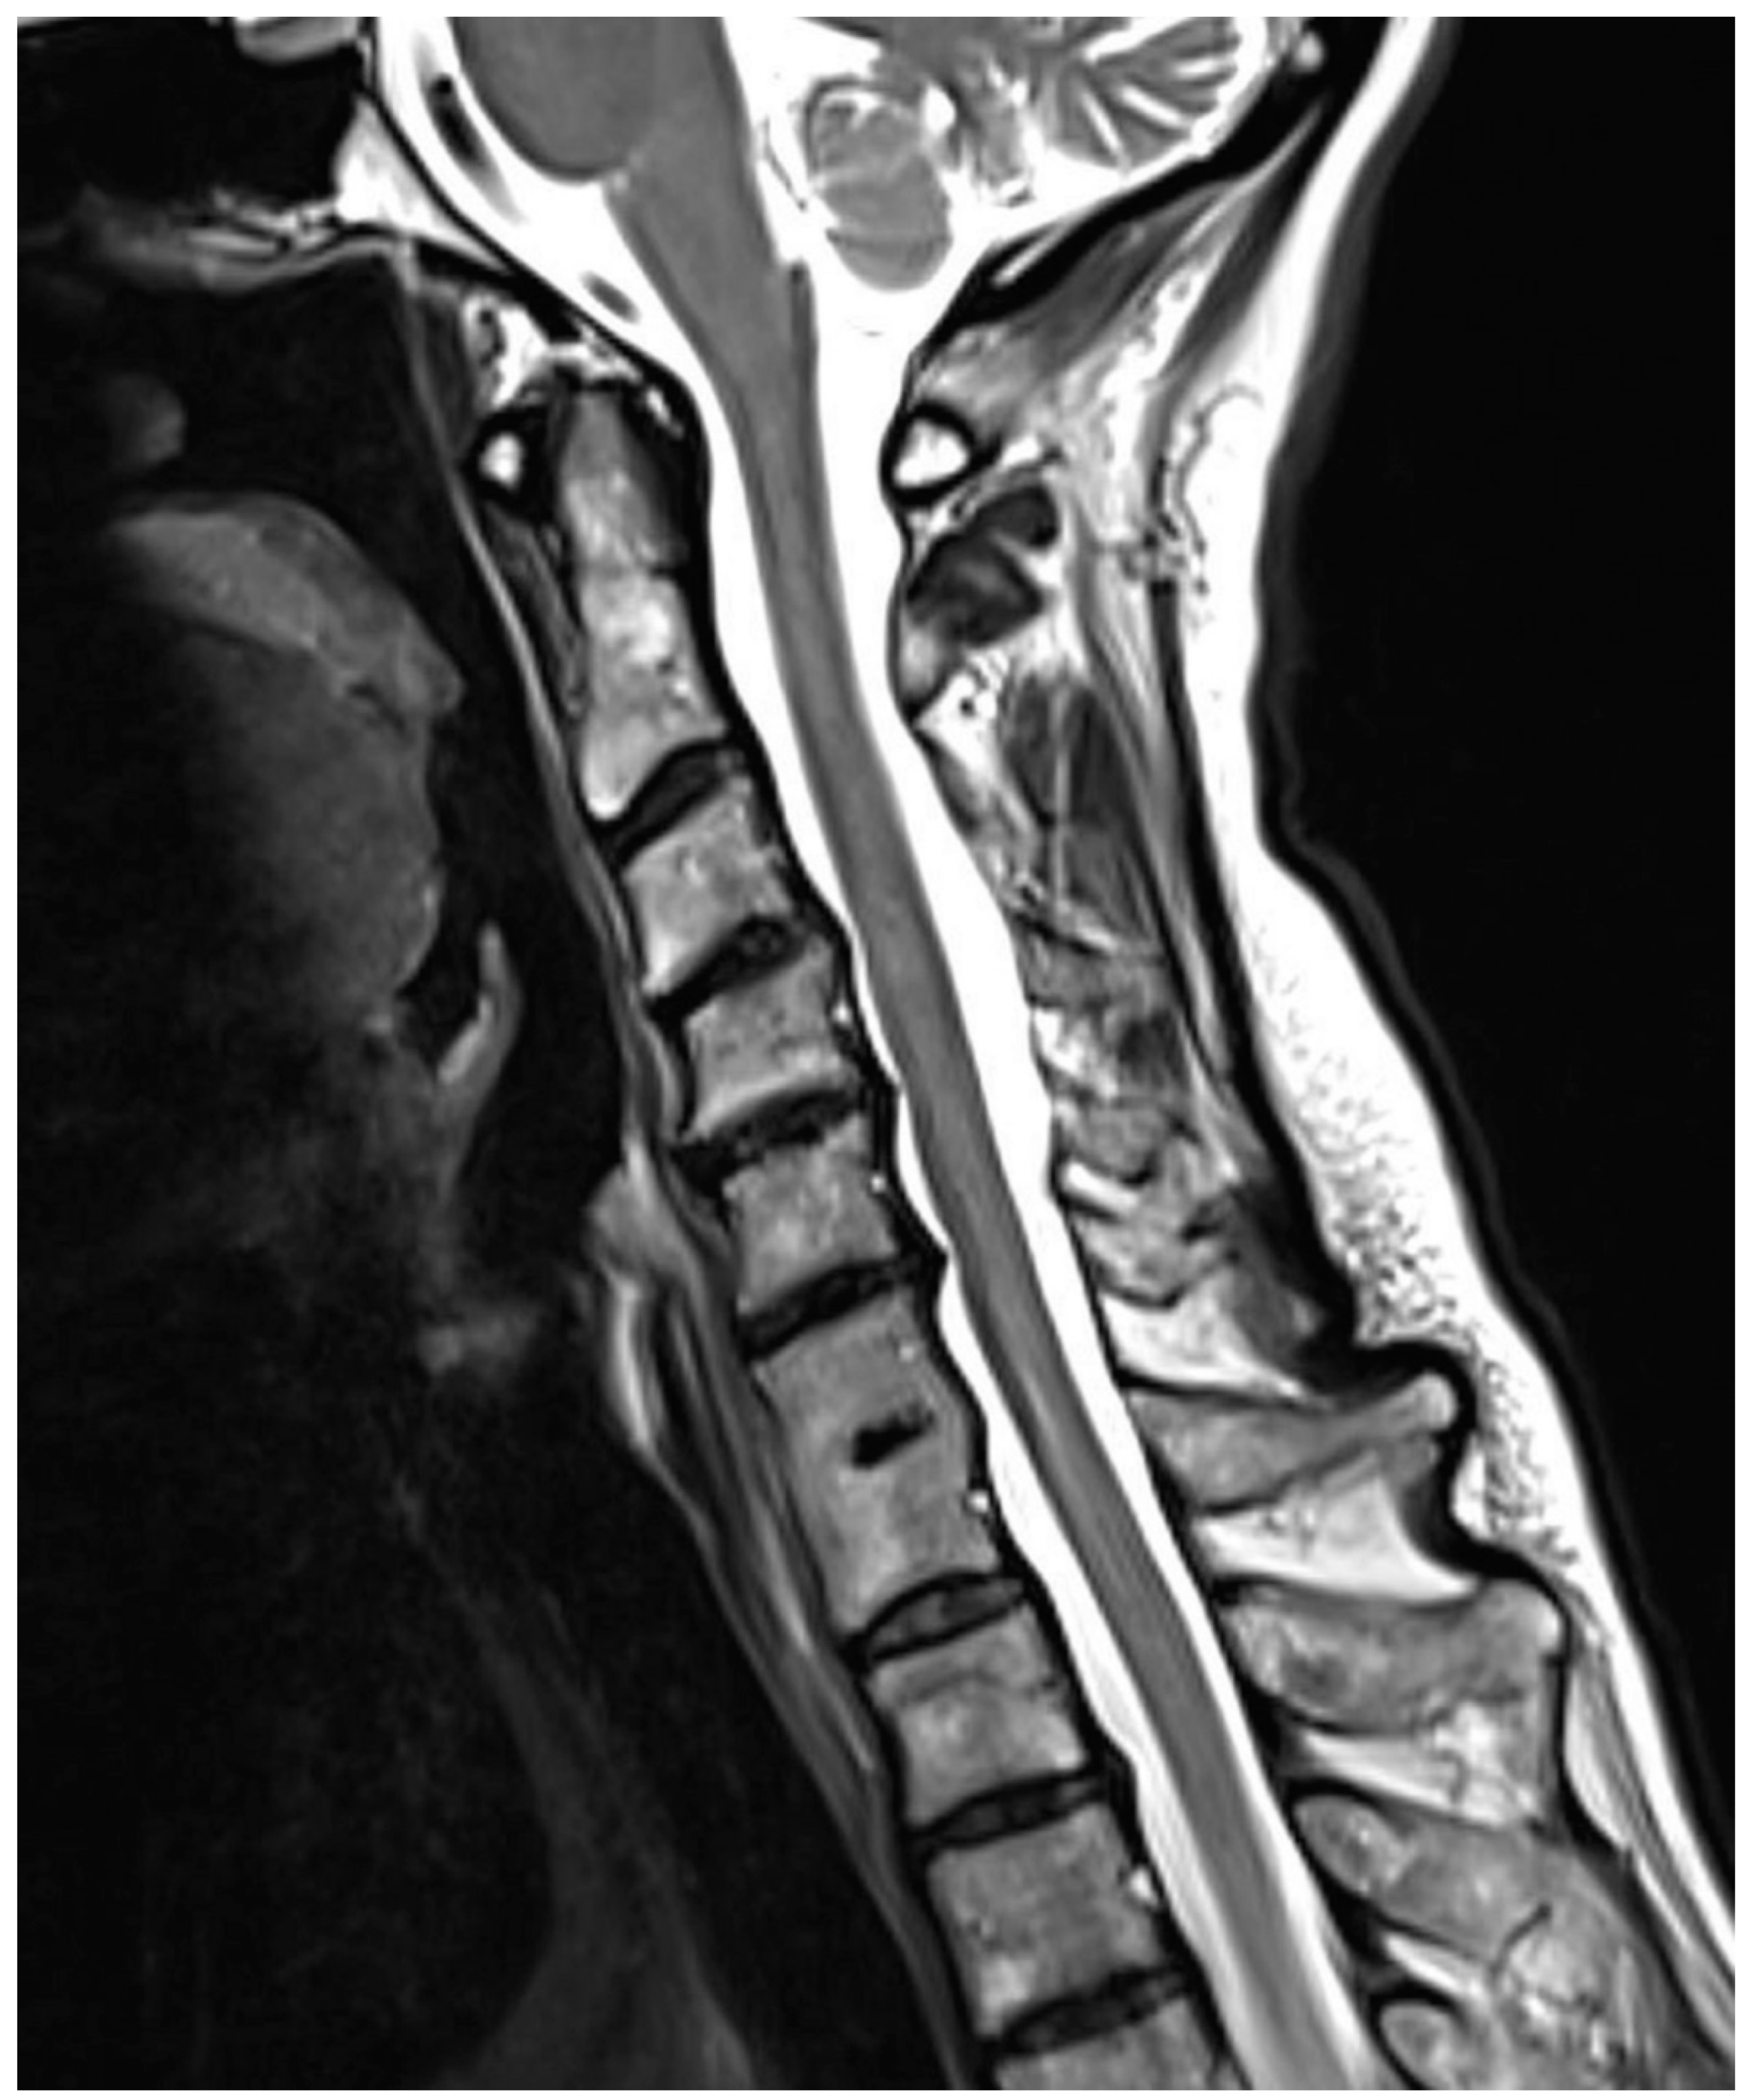

Are Congenital Cervical Block Vertebrae a Risk Factor for Adjacent Segment Disease? A Retrospective Cross-Sectional CT and MR Imaging Study